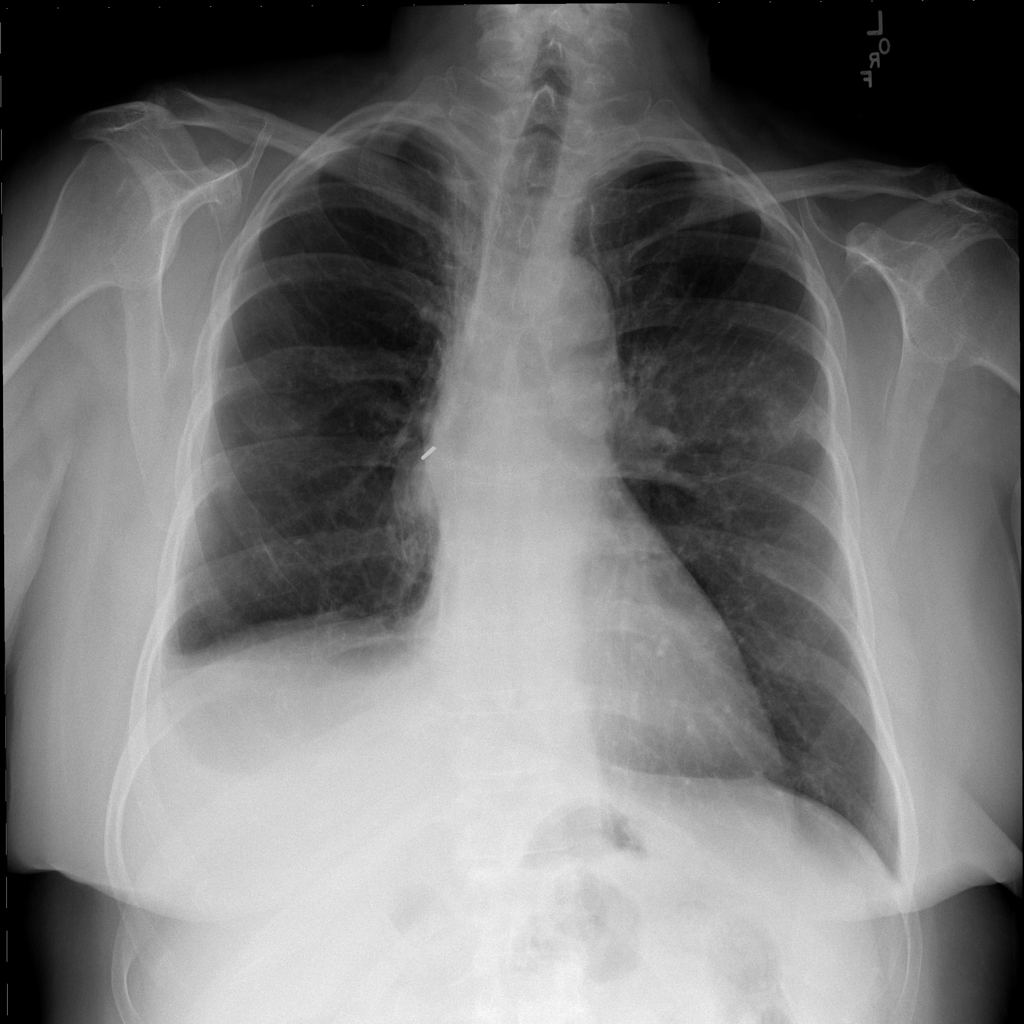

PAT-C0E5 · IMG-001Mass

PAT-C0E5 · IMG-001

PA